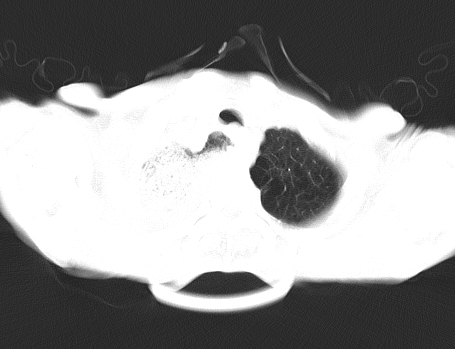

以下是引用gaoshengjiang在2008-5-30 19:53:00的发言:[br]右上叶可见大片实变影,其内可见充气支气管影及囊状影,右上叶尖端支气管走形区可见结节样影,左侧胸腔内可见胸腔胃影。纵隔淋巴结肿大。[br]考虑:1.右上肺阻塞性肺炎伴肺脓肿形成。支持转移所致。[br] 2.左侧胸腔胃。